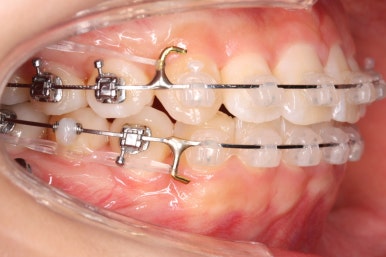

화살표에 보이는 부착물의 이름이 바이트터보 입니다.

깊게 맞물리는 앞니, 즉 과개교합을 개선하기 위해 일시적으로 이용하는 장치입니다.

굉장히 효율적으로 과개교합을 개선할 수 있습니다.

아랫니에도 이제 장치를 붙였습니다.

과개교합인 채로 아랫니에도 장치를 붙이게 되면 아랫니 장치가 깨물려서 다 떨어지거나 부서지기 쉽습니다. 따라서 바이트터보는 굉장한 역할을 하게 됩니다.

눈으로 보기에는 과개교합이 개선이 된 것처럼 보이지만 아직은 아닙니다. 바이트터보가 남아있는 채로도 어금니가 맞물려야 진짜로 개선된 것이죠.